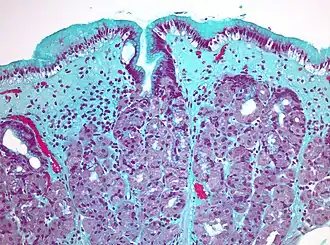

Бронх крысы, окраска трихромом Массона